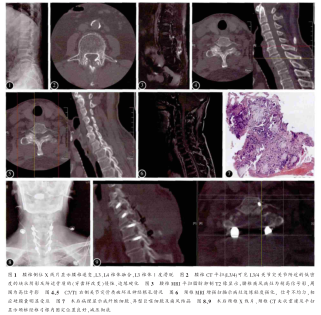

实验室检查:尿素氮5.4mmol/L,肌酐68.0μmol/L,尿酸642μmol/L,葡萄糖:6.1mmol/L,白细胞计数12*109/L,血沉6mm/h,C-反应蛋白:77.4mg/L,HLA-B27>40u/ml,类风湿因子:41IU/ml。影像学检查:X线片显示“L4椎弓根骨质破坏,L5椎弓根双侧峡部裂”(图1a)。腰椎CT平扫+重建显示“L4双侧椎弓骨质破坏;L5双侧椎弓根峡部断裂,L4/5椎管内病灶侵犯,椎管狭窄”(图1b)。腰椎MRI示“L4附件骨质信号不均匀,边界清,周围软组织肿胀,增强扫描病变区未见明显强化,周围软组织可见轻度强化,病变平面椎管狭窄,神经受压”(图1c)。术前评分:VAS腰痛评分6分,VAS下肢疼痛评分7分。JOA评分(15分)3分。

经术前充分准备,按照脊柱痛风为首选诊断处理,不排除腰椎肿瘤的可能,因此拟定气管插管全麻下手术治疗,手术方案拟定:(1)腰椎痛风病灶清除、椎管减压、椎弓钉固定、植骨融合术;(2)腰椎肿瘤病灶清除、椎管减压、椎弓钉固定、植骨融合术。术中所见广泛的“白色泥沙样”结晶物如图1d、e,包括腰椎双侧关节突(L3/4、L4/5、L5/S1),关节面、关节囊、黄韧带、后纵韧带及腰椎骨,考虑为炎性刺激所致,极易出血,手术出血量约800ml。术后病理:组织内大量结晶样物质并钙化,伴有肉芽组织生成,符合痛风结节样改变如(图1g、h)。术后患者神经损伤症状明显好转,左下肢放射性疼痛完全消失,左侧直腿抬高试验阴性,感觉减退区较术前好转。尿酸在术后3d恢复正常。术后2周:VAS腰痛评分2分,VAS下肢疼痛评分1分,JOA评分(15分)10分;术后3个月:VAS腰痛评分0分,VAS下肢疼痛评分0分。JOA(15分)13分;术后9个月:VAS腰痛评分0分,VAS下肢疼痛评分0分,JOA(15分)14分,仅部分肌力未恢复正常。随访期间未出现新的并发症。